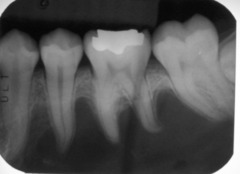

radicular cyst

-asymptomatic radiolucency associated with the root of a NONVITAL tooth

periapical granuloma

-asymptomatic, tooth sensitive to percussion, slight extrusion of tooth -radiographically: slight thickening PDL and periodontal radiolucency CHRONIC